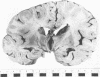

A case is reported of a 52 year old man who sustained a head injury and survived for three years and two months in coma. He was subsequently shown to have severe brain stem damage, with a bilateral lesion of the central tegmental tract and bilateral hypertrophic olivary degeneration, associated with a widespread loss of Purkinje cells in the cerebellar cortex. Hypertrophic olivary degeneration is considered to be a trans-synaptic change associated with a lesion of the central tegmental tract, which in this case was thought to be due to primary shearing injury of the brain stem involving the superior cerebellar peduncles. It is suggested that, as a consequence of long survival, Purkinje cell degeneration represents further trans-synaptic changes, the result of neuronal degeneration in the hypertrophied inferior olivary nuclei and in the dentate nuclei. A chain or `circuit' of degenerated neurones is thereby produced.